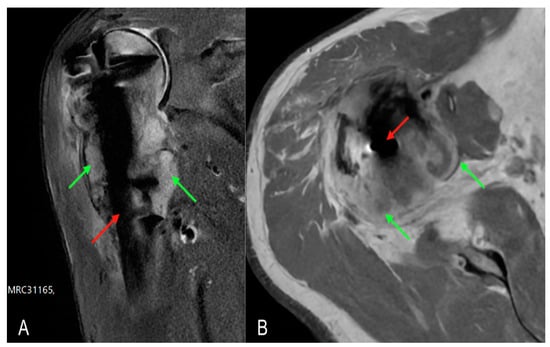

A 62-year-old male patient was taken to the emergency room of the Scientific Institute for Research, Hospitalization and Health Care (IRCCS) Galeazzi Orthopaedic Institute (Milan, Italy) for pain and functional impotence in the right shoulder following an accidental fall at home with direct trauma to the upper limb. During the anamnestic collection, the patient reported being affected by arterial hypertension and hypercholesterolemia. He also reported having suffered a previous ST-elevation myocardial infarction (STEMI), treated with drug-eluting stent implantation. The patient reported episodes of fever, weight loss, and asthenia in the year preceding the traumatic event. A shoulder radiograph with standard projections was performed, which allowed for the diagnosis of a humeral surgical neck fracture, classifiable as type 11-A2.2 according to the AO/OTA Fracture and Dislocation Classification revised in 2018 (Figure 1A). The results of routine blood tests performed on admission were normal. Two days after the traumatic event, the patient underwent surgery to reduce and fix the fracture with a T2 ® model 8 mm × 150 mm intramedullary nail and screws (Stryker, Kalamazoo, MI, USA) (Figure 1B) under general anaesthesia. The immediate postoperative course was regular, with good control of painful symptoms and reported subjective well-being. On the second postoperative day, the patient was discharged with indications for clinical follow-up (FU) and periodic radiographs.

Figure 1. Right shoulder X-rays: (A) anteroposterior radiograph of the shoulder showing a surgical neck fracture of the proximal humerus (arrow); (B) antero-posterior radiograph of the postoperative shoulder showing reduction of the major fracture fragments and fixation with T2 ® model 8 mm × 150 mm intramedullary nail and screws (Stryker, Kalamazoo, MI, USA).